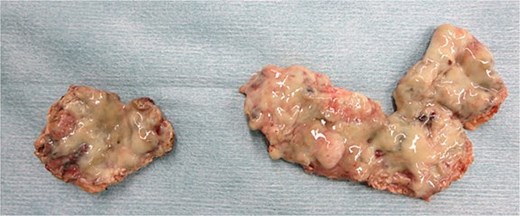

Emergency laparoscopic surgery was initiated for diffuse peritonitis. Although copious purulent ascites was observed, no gastrointestinal perforation was identified. Instead, two perforations with purulent discharge were found in the enlarged uterine body, confirming ruptured pyometra (Fig. 2a). Given the patient’s advanced age, comorbidities, and hemodynamic instability, hysterectomy was considered excessively invasive. The uterine wall was therefore incised, and purulent material was drained (Fig. 2b). Partial resection of the uterine wall was performed to maintain an open abscess cavity and facilitate continuous drainage (Fig. 2c). The abdominal cavity was irrigated with 8 L of warm saline, and drains were placed in the bilateral subdiaphragmatic spaces, uterine cavity, and Douglas pouch. Operative time was 2 h 4 min with minimal blood loss. Histopathology showed inflammatory cell infiltration with edema and necrosis, without evidence of malignancy (Fig. 3).

Laparoscopic surgical images of the case: (a) Two perforations in the uterine body, sites of purulent discharge. (b) Findings after incising the uterine muscle layer to connect the two perforation sites and draining the cavity. (c) Findings after partial resection of the uterine wall.

Resected uterine wall: An abscess adherent to the inner surface of the resected uterine wall.